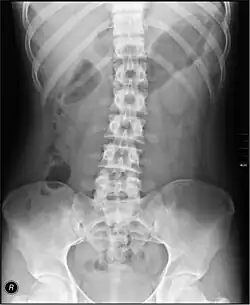

The standard abdominal X-ray protocol is usually a single anteroposterior projection in supine position.[15] A Kidneys, Ureters, and Bladder projection (KUB) is an anteroposterior abdominal projection that covers the levels of the urinary system, but does not necessarily include the diaphragm.

- The spine (that is, the vertebral column. A projectional radiograph of the spine confers an effective dose of approximately 1.5 mSv, comparable to a background radiation equivalent time of 6 months.

- Lumbar Spine - AP and Lateral +/- L5/S1 view in the UK, with obliques and Flexion and Extension requests being rare.[15] In the US, basic projections include an AP, two Obliques, a Lateral, and a Lateral L5-S1 spot to better visualize the L5-S1 interspace. Special projections are AP Right and Left bending, and Laterals with Flexion and Extension.

- Pelvis - AP only in the UK, with SIJ projections (prone) on special request.[15]